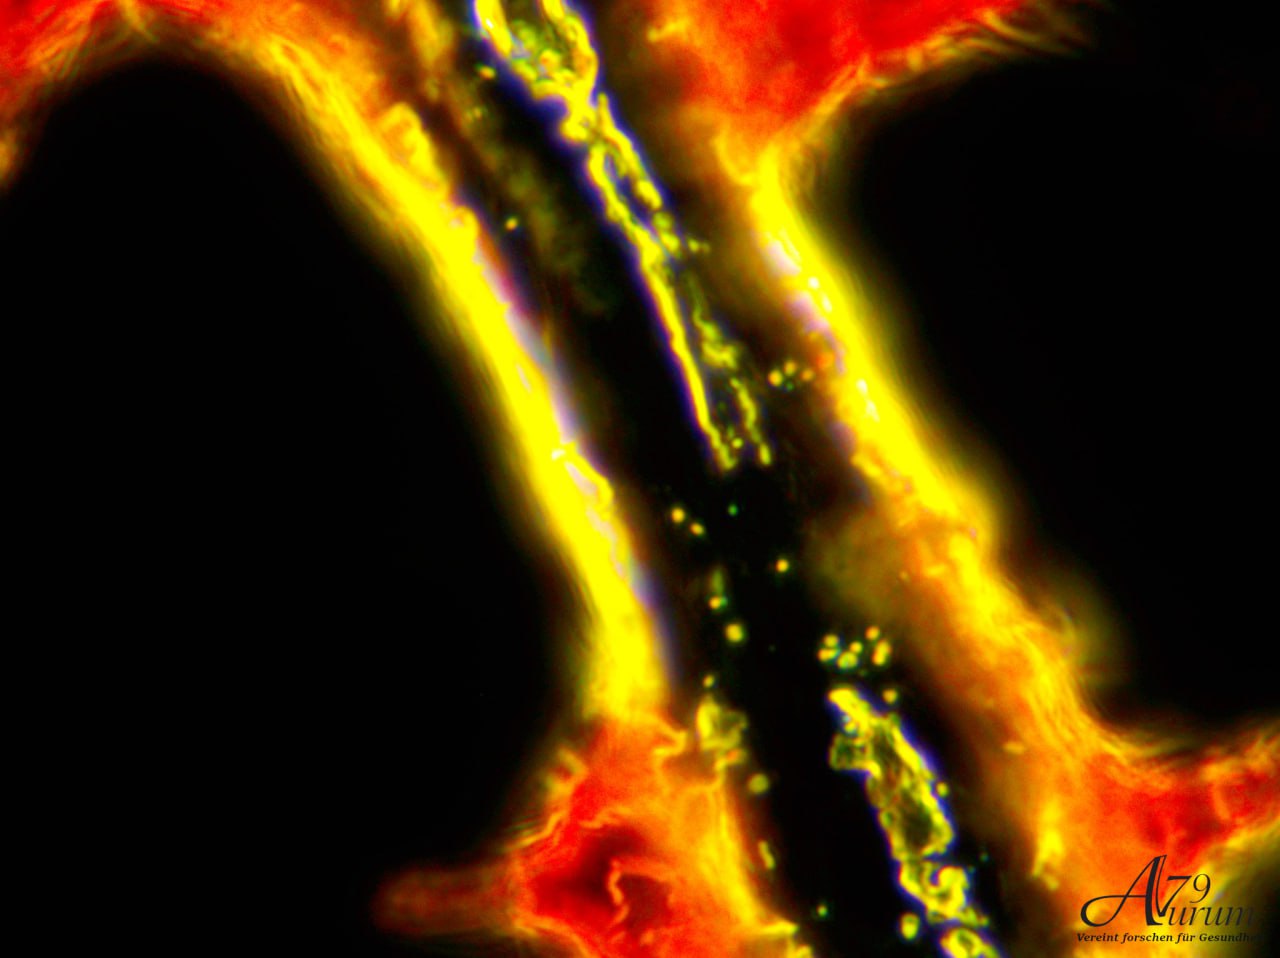

Vitalblutanalyse 1. Tag

Dichtem Vorkommen von kreisförmigen Zellen. Leichte Aggregationen sichtbar, aber keine eindeutigen abnormalen Formen oder Parasiten erkennbar. Weitfeld-Okulare mit 10-facher Vergrößerung & 10x Objektiv

Zeigt zahlreiche kreisförmige Strukturen (Erythrozyten) mit variierender Intensität. Einige Zellen scheinen aggregiert, andere einzeln verteilt. Weitfeld-Okulare mit 10-facher Vergrößerung & 40x Objektiv